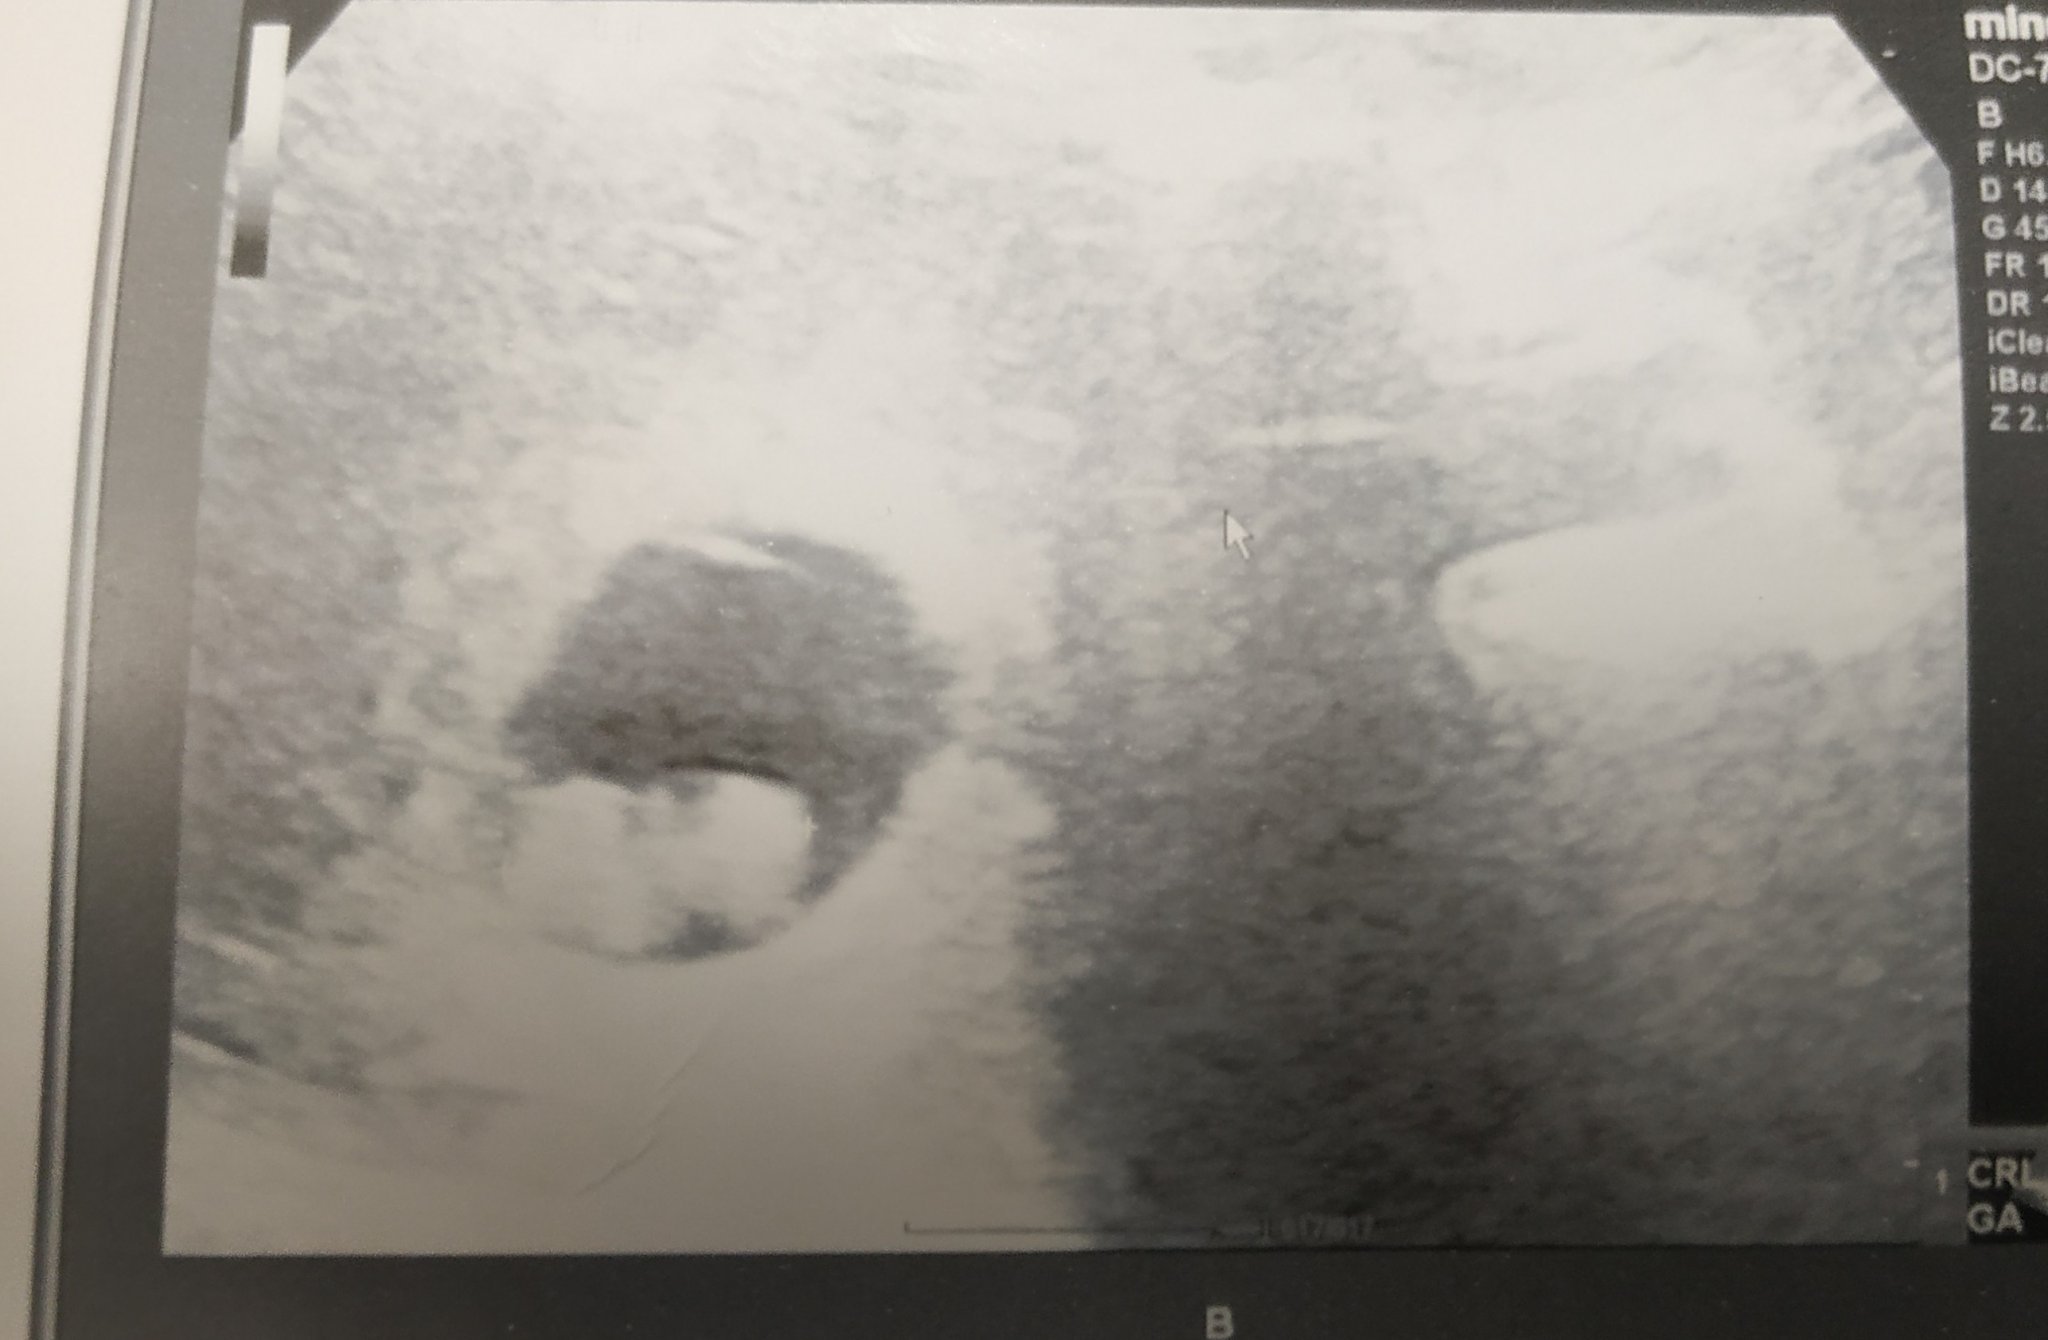

Как мога да определя датата на термина, когато цикълът ми е нередовен?